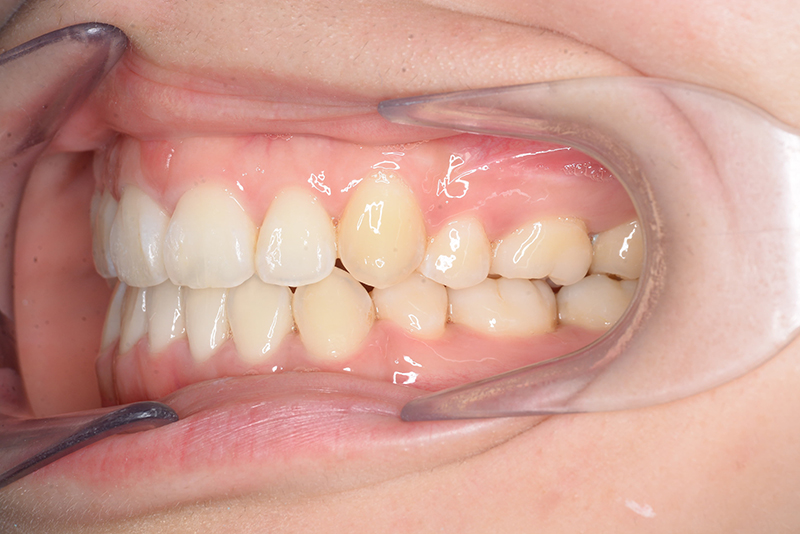

| 口腔内所見 | over jet 4.5mm、over bite 4.0mm、大臼歯関係 I級で上下顎前歯部に叢生が認められた。 |

| 批評・予后 | 叢生が大きかった影響もあり、治療期間は20ヶ月と比較的短い期間が終了できた。治療後においては口元の改善、咬合の緊密化は達成できたように思う。 |